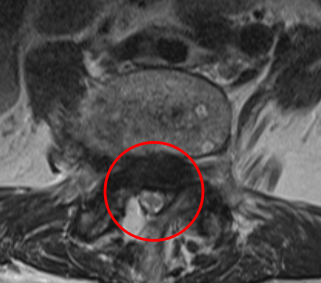

治療前

┃検査・診断

腰椎MRIの画像を確認したところ、L5とL4の腰椎がずれてしまっており、L4/5の脊柱管が圧迫されていました。そのため、痛みと痺れの原因は、すべり症に伴う脊柱管狭窄症と診断しました。